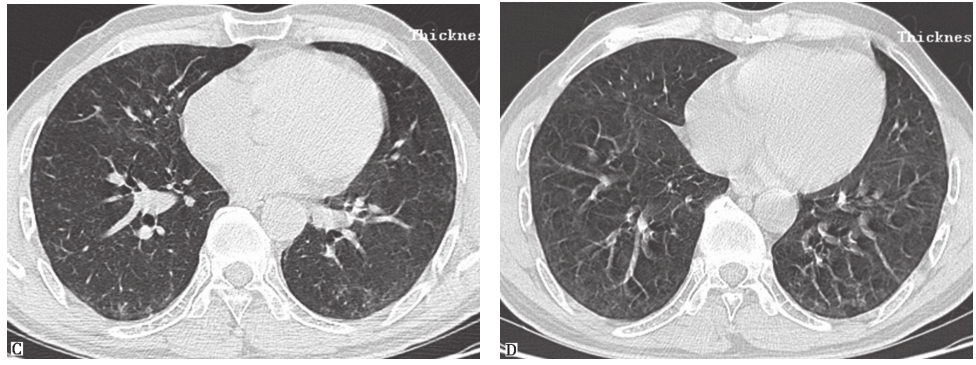

患者经泼尼松(20mg,每天2次)口服治疗,并且脱离原有工作环境,1个月后复查胸部HRCT示两肺磨玻璃影及小结节影较前进一步吸收(图17),咳嗽、气喘症状明显缓解。

图17泼尼松治疗1个月后胸部HRCT表现

HRCT显示磨玻璃影及小结节影进一步减少,双肺胸膜下少量小结节影